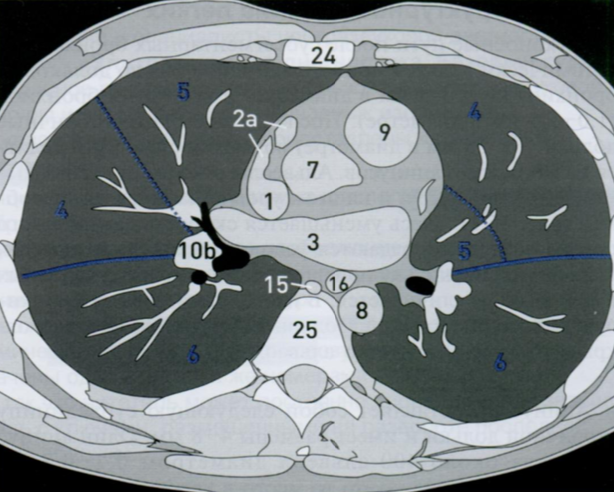

КТ грудной клетки №3

Назовите все анатомические структуры, которые Вы знаете, на данном КТ срезе (10).

Найдите грудные позвонки и грудину. Затем верхнюю полую вену, восходящую и нисходящую аорту, легочный ствол, левое предсердие и легочные сосуды, непарную вену и пищевод.

A

26 - грудные позвонки

24 - грудина

1 - верхняя полая вена

7 - восходящая аорта

9 - легочный ствол

3 - левое предсердие

10 - сосуды легких

8 - нисходящая аорта

15 - непарная вена

16 - пищевод

Синим цветом отмечены номера сегментов.